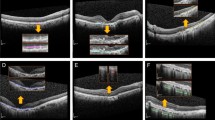

In both models, CAM was able to identify the pathologic region on OCT successfully, based on the generated heat map (Fig. 4). Additionally, in the second model, the learning stabilized faster with transfer learning than with CNN (Fig. 5).

Heat maps for two CNN classification models. a Heat map for the first model for classifying normal and AMD OCT images, b heat map for the second model for classifying the presence or absence of any fluid. CAM was able to identify characteristic areas on the OCT, and it is presented as a heat map. CAM class activation mapping, AMD age-related macular degeneration, CNN convolution neural network, OCT optical coherence tomography